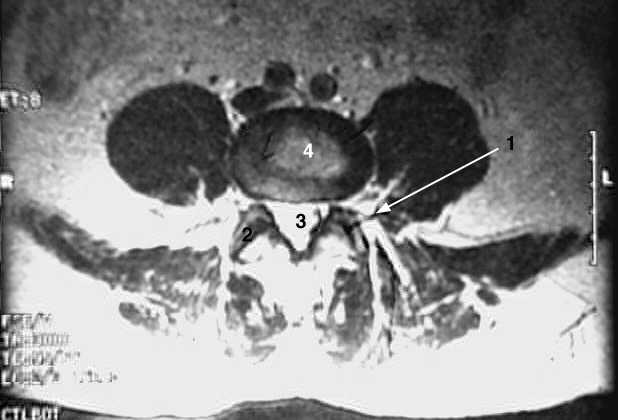

Back- Lumbar cross zoom:

1. Arrow: intervertebral foramen

2. Facet joint

3. Spinal canal with contrast material

4. Vertebral body.